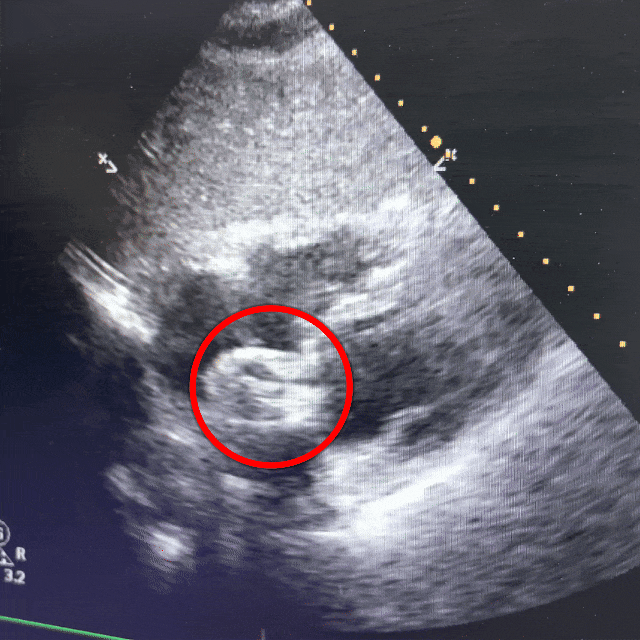

超声双房心切面下可见封堵器双盘骑跨在房间隔两侧

双房心切面

超声下可见封堵器稳定夹持在房间隔两侧,盘面贴合,形态良好